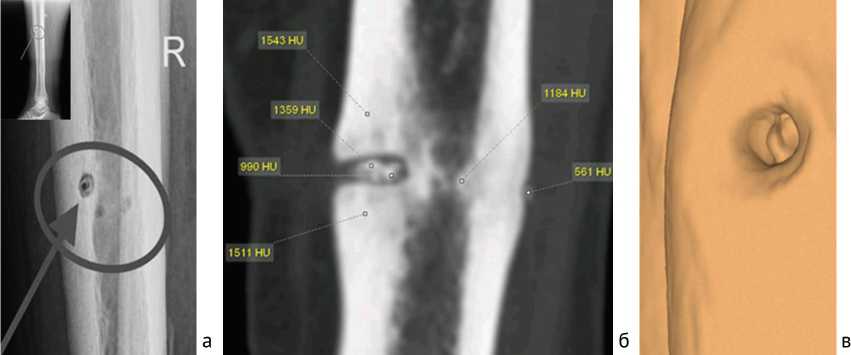

Характерное расположение «замурованного» секвестра в корковой пластинке при локализации воспаления на уровне средней трети диафиза, выявленное при МСКТ, наблюдали у пяти пациентов из основной группы. Данный тип секвестра представляет собой узкий кольцевидный участок омертвевшей кости, окружённый рентгенопрозрачным ореолом, что является характерным признаком активного инфекционного процесса и реактивного воспаления в окружающих тканях. Мы пришли к такому заключению на основании сопоставления МСКТ-изображений с клиническими данными и результатами микробиологического исследования, подтверждающими наличие инфекции в очаге. В литературе подобные секвестры описываются как «пуговчатые» из-за их формы и ограниченного размера [17, 18, 19] (рис. 6).

Рис. 6. Рентгенограмма голени пациента 46 лет со СО в боковой проекции, кольцевидный, «пуговчатый» секвестр (а); МСКТ голени пациентки 52 лет со СО, замурованный секвестр, MPR во фронтальной плоскости (б); 3D-реконструкция, наглядное представление о кольцевидном «пуговчатом секвестре» (в)

Частота выявления таких «пуговчатых» секвестров в нашей выборке составила около 15 %. Размеры и форма секвестров в области метафиза и диафиза значительно отличались. В области диафиза секвестры чаще имели форму, приближенную к прямоугольнику, горизонтальная сторона которого была в два–три раза длиннее. В области метафиза секвестры в 85,6 % случаев имели неопределенную форму различного размера, но не больше 5 мм в 80,5 % случаев. Секвестры в различных участках кости отличались по плотности. В метафизарном отделе плотность составляла (652,4 ± 45,8) HU, в области диафиза — (1388,6 ± 92,7) HU ( p < 0,01).

Для СО в области диафиза характерны также так называемые «замурованные» секвестры в кортикальной пластинке, которые повторяют контуры спицевого канала и напоминают при исследовании методом МСКТ (3D) «пуговчатый секвестр». Этот феномен подтверждается и данными других исследований, где подобные формы секвестров описаны при локализации воспаления в кортикальном слое кости на ранних стадиях хронического остеомиелита [13, 14].